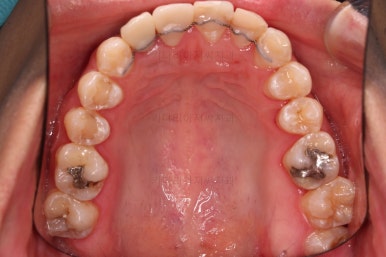

초진 시 입안의 모습입니다.

화살표는 결손 부위, 동그라기믄 유치잔존과 매복치아 부위입니다.

동그라미는 유치가 있는 상황이었는데요. 잇몸도 많이 파괴되어 있었고, 유치 자체의 상태도 좋지 못했어요.

해당 모습을 X-ray로 보면요.

앞니 부러진 부위, 어금니 결손 부위가 명백히 보이죠.

동그라미 부분은 상한 유치가 보이는데, 그 하방으로 영구치가 매복되어 올라오지 못하고 있는 상태였어요.